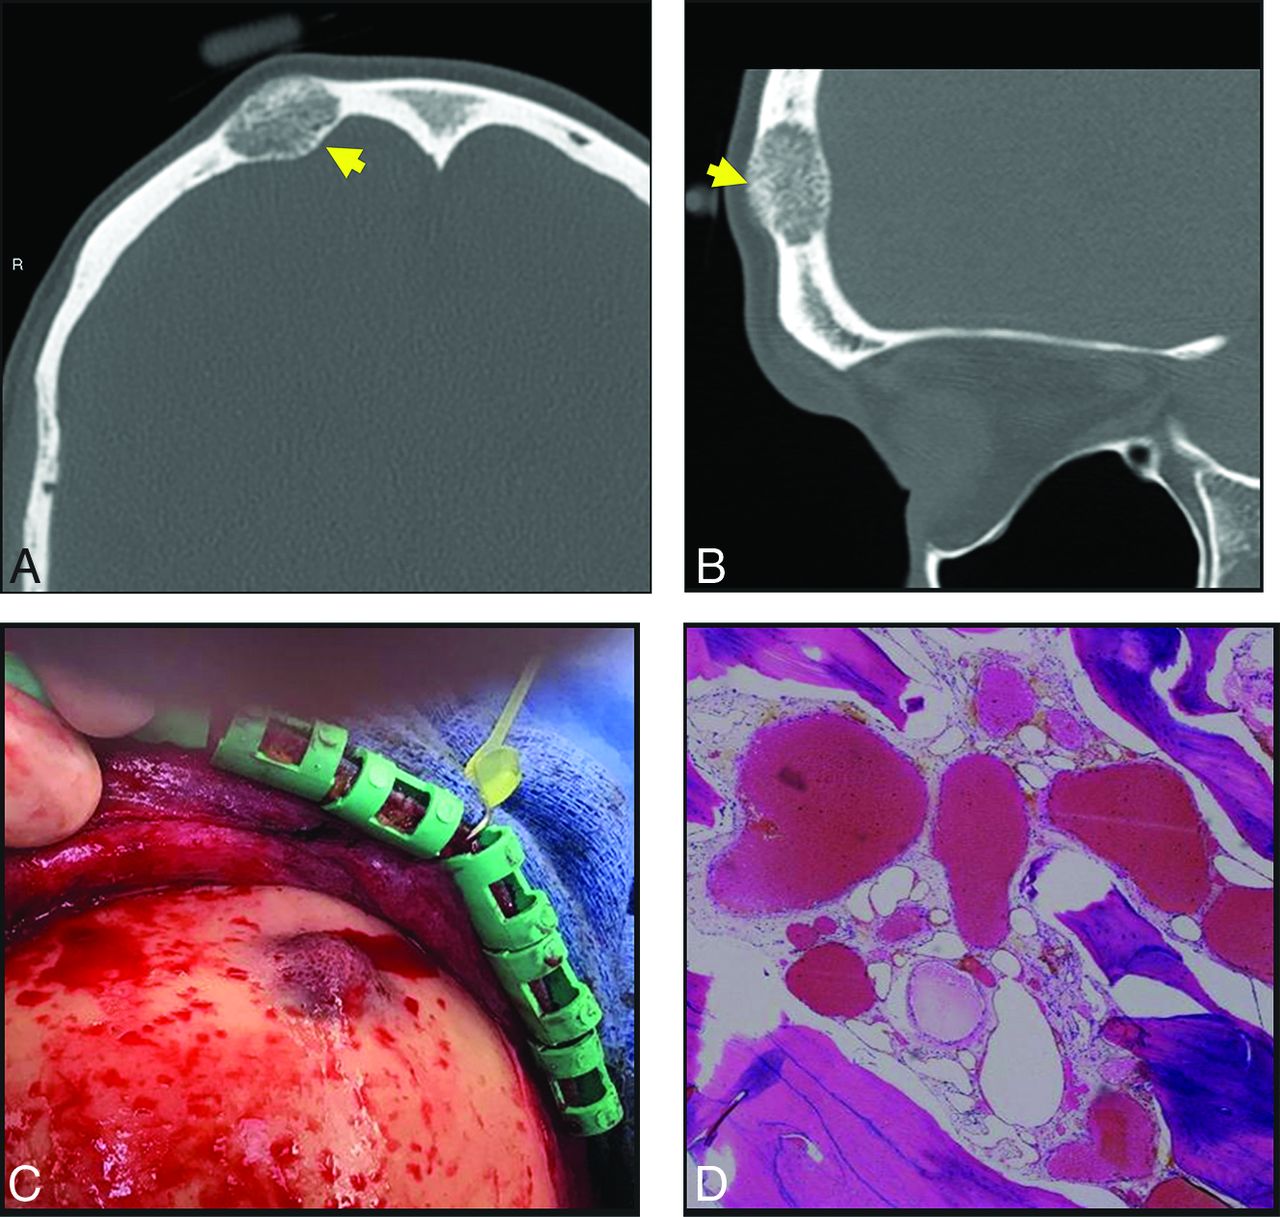

A 40-year-old man with a palpable frontal bump. Axial (A) and sagittal (B) thin-section CT images demonstrate a typical expansile lucent lesion with internal spiculated calcification (yellow arrow, A and B). Intraoperative photograph (C) shows a raised, red, porous-appearing calvarial lesion. H&E-stained photomicograph (D) shows dilated cavernous blood-filled spaces lined by flattened epithelium, characteristic of a venous malformation. There is focal hemosiderin staining, which is evidence of prior hemorrhage.